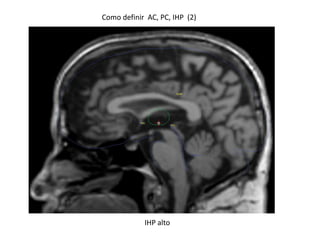

Como definir AC, PC, IHP (2)

IHP alto